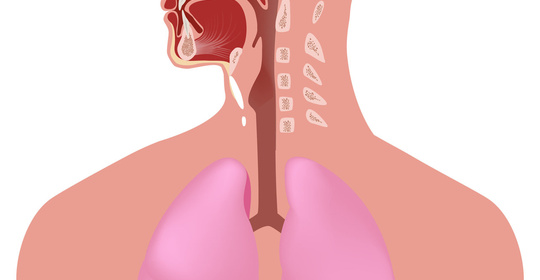

兒童肺炎檢查心電圖異常

兒童出現肺炎時進行心電圖檢查可發現異常結果,可能與肺炎本身有關,也可能與肺炎無關。家長需要及時帶患兒到醫院就診,在醫生的指導下完善相關檢查並明確具體原因。